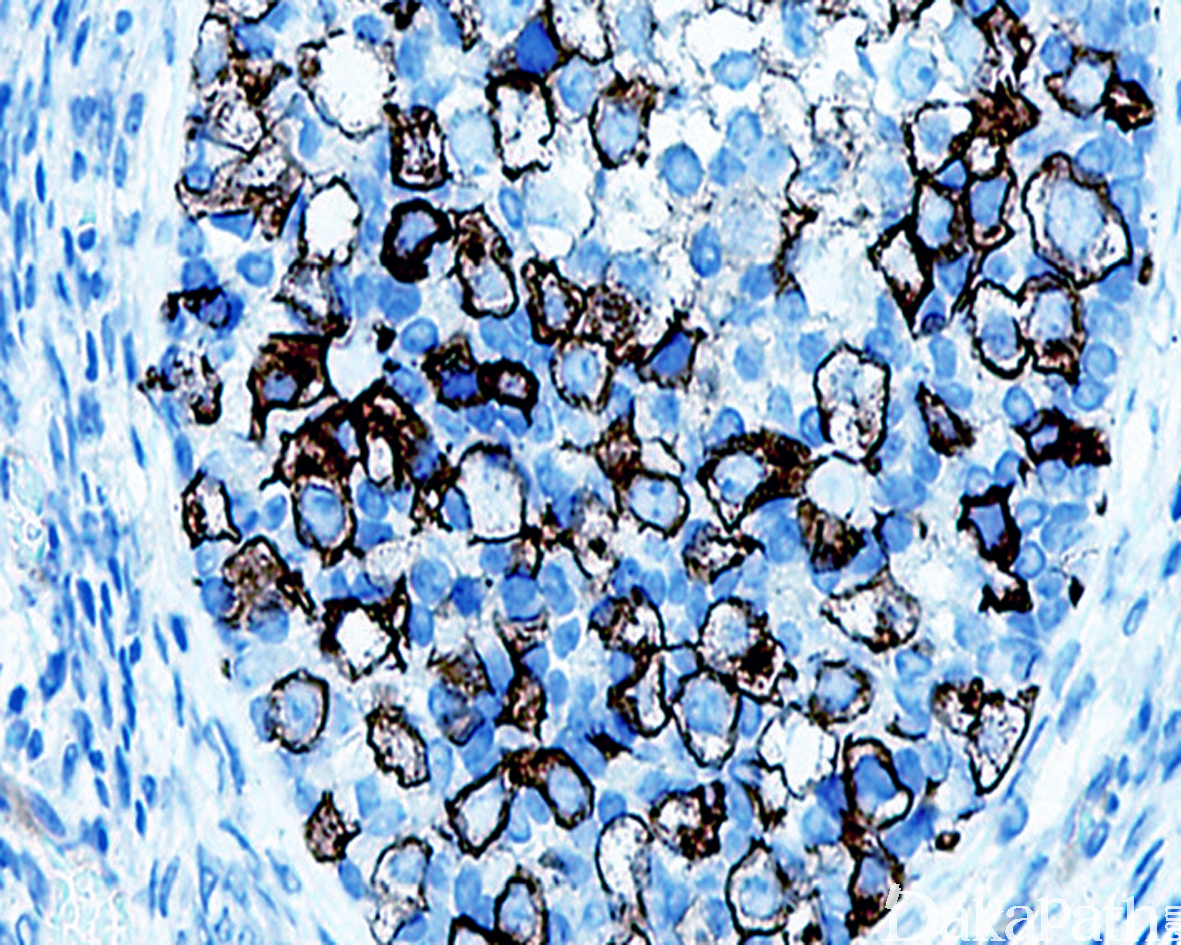

免疫组织化学染色:

生殖细胞不同程度表达 PLAP、OCT3/4. NANOG、AP-2γ、 VASA、TSPY、CD117. KIT-L,性索细胞表达核 FOXL2. calretinin 和 Inhibin,弱表达 SOX9。